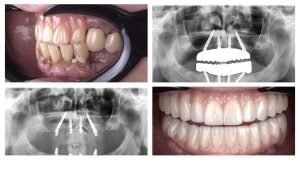

Case: Buccaly Displaced Flap

Initial state – Patient lost central incisor some time ago Intraoral Scan – clearly visible…